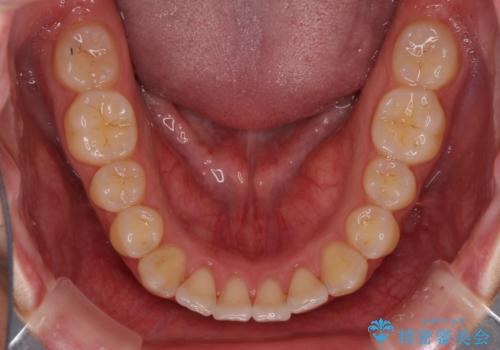

- 前歯の歯並びと不自然な色をした前歯のクラウンを気にして来院された患者様です。

上下前歯の歯列不正はインビザラインにより歯列を整え、その後に、前歯をオーダーメイドタイプのオールセラミッククラウンにて補綴治療することとしました。

初診時には、歯並びを整えることのみを検討されていましたが、歯列が整うにつれて不自然な色合いが気になるようになり、矯正治療を行ってから補綴治療をする計画を受け入れてくださいました。